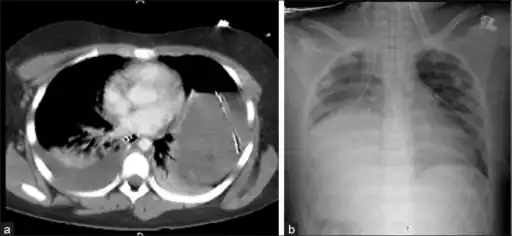

Bilateral blunt diaphragmatic rupture a) confirmation of intrathoracic herniation indicates left hemidiaphragmatic rupture b) post operative image shows elevation of right hemidiaphragm adding suspicion of right diaphragmatic rupture -

Axial lower chest CT scan showing bowel herniation due to left diaphragmatic rupture